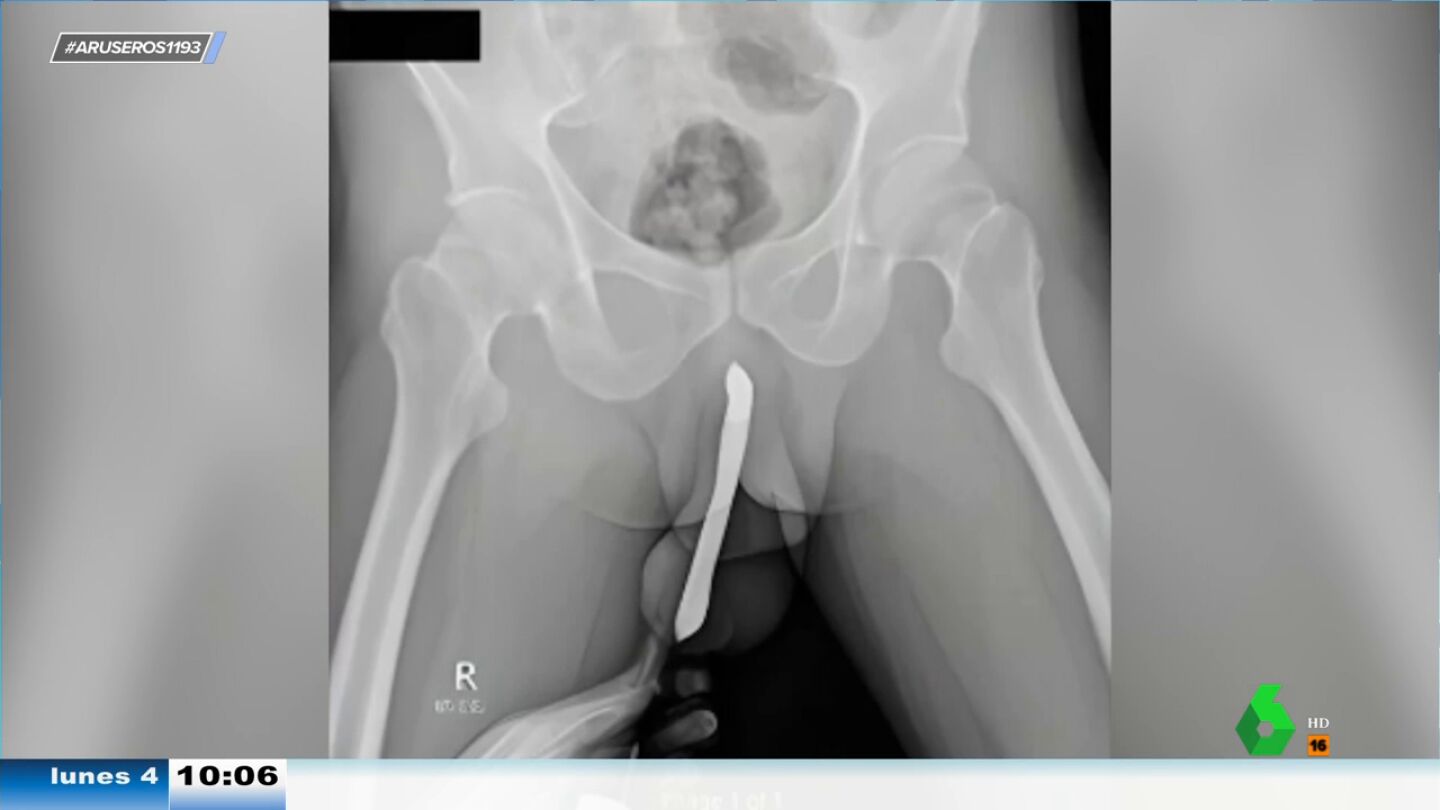

Las radiografías que pueden verse en el vídeo principal de esta noticia pertenecen a un hombre indonesio de 43 años. En ellas puede verse con claridad que tiene un cepillo de dientes alojado debajo del prepucio. Así nos cuentan la noticia en Aruser@s.

Este hombre de 43 años ha tenido que someterse a una cirugía extractora después de que se le rompiera un cepillo de dientes en el interior del pene. "No en el interior del ano. ¡En el interior del pene!", insiste Alfonso Arús tras ver las radiografías que lo demuestran con una claridad pasmosa.